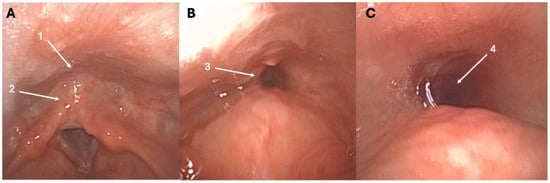

The first cases of retrograde cricopharyngeal dysfunction (R-CPD) were published at the end of the 1980s [1,2], while the first case series identifying R-CPD as a specific syndrome was just published in 2019 [3]. In this first case series of patients with an inability to burp, Bastian and Smithson proposed that R-CPD is related to the loss of the belch reflex, which leads to troublesome symptoms [3]. This reflex is normally a physiological response to gaseous pressurization of the esophagus. Such pressurization occurs when transient lower esophageal sphincter relaxation allows gas from the stomach to reach the esophagus. If the upper esophageal sphincter fails to relax during this pressurization, gas becomes trapped in the esophagus. This trapped gas is subsequently carried back into the stomach by peristalsis in individuals without significant dysmotility, while in individuals with lost esophageal peristalsis, the gas can be blocked in the esophagus. Both retrograde processes may cause characteristic symptoms of varying severity. These symptoms include gurgling noises, bloating, chest pain, and excessive flatulence, which are typically accompanied by the inability to burp [3,4,5]. The fiberoptic examination of R-CPD patients is commonly unremarkable; however, some patients report a “tunnel sign” at swallowing during the nasofibroscopy (Figure 1). The tunnel sign reflects entrapped gas in the esophagus that cannot be eructated. To date, the etiology of R-CPD remains unelucidated, with recent studies suggesting a potential role of childhood reflux disease in cricopharyngeal and upper aerodigestive tract irritation and related protective airway mechanisms (cricopharyngeal muscle hypercontractility) [4,5].

Figure 1. Tunnel sign throughout the nasofibroscopy. At rest, the entry of the esophagus (1) and retrocricoid region (2) appear normal (A). During swallowing, the tunnel sign may appear, reflecting the entrapped gas into the esophagus (3)—(B), (4)—(C), and could be a highly specific sign of R-CPD. The patient was a 27-year-old female with a childhood history of R-CPD, gurgling noises, chest pain, bloating, and flatulence.